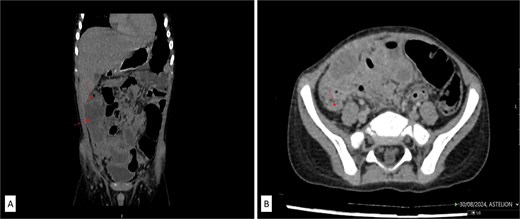

On examination, he was febrile, tachypneic, tachycardic, and hypotensive. Abdominal examination revealed a rigid abdomen with a palpable mass and marked tenderness and guarding in the right abdomen. Laboratory results indicated a leukocyte count of 19 × 109/μl, significantly elevated C-reactive protein (210 mg/dl), and a platelet count over 1 000 000/mm3, with normal coagulation tests. Abdominal ultrasound revealed echogenic fluid, prominent and hyperechoic mesenteric and omental fat, and a mass occupying the right abdomen from the subhepatic region to the pelvis. Contrast-enhanced CT of the abdomen confirmed a right abdominal mass adherent to the posteroinferior surface of the liver’s right lobe, cecum, terminal ileum, and right pelvis (Fig. 1A and B), but the appendix was not visualized. Inflammatory changes in the adjacent mesenteric fat were also noted.

(A) Contrast-enhanced abdominal CT in coronal and axial scans showed an irregularly shaped mass in the right abdomen (labeled) in the form of extensive inflammatory mass which is in the close contact with the inferior liver surface, involving parts of ascending colon, cecum, and terminal ileum. (B) Retrocecal tubular structure (labeled) inseparable of dorsal wall of coecum which can correlate to the operative findings of second appendix.

Following fluid resuscitation and antibiotic administration, a laparotomy was performed via a McBurney’s incision. Intraoperatively, purulent peritonitis with fibrin-purulent membranes and a diffuse mass in the right abdomen were observed. The appendicular infiltrate and periappendicular abscess extended from the subhepatic region to the right pelvis (Fig. 1A and B). The surgical treatment of periappendicular abscess included the evacuation of all visible pus and exudates and conducted a thorough rinse with warm saline until the outflow was free of contaminants and the operation bed was clean. Despite technical challenges due to adhesive bowel loops, distorted anatomy, and inflammation affecting a wide area in the abdominal cavity—including the cranial position of the appendix on the cecal tenia above the ileocecal valve—we successfully performed an appendectomy, submitting the fragmented perforated appendix for histopathological analysis. During further exploration, a second, retrocecal appendix approximately 30 mm long was found, attached to the cecum without visible signs of inflammation, and was resected.